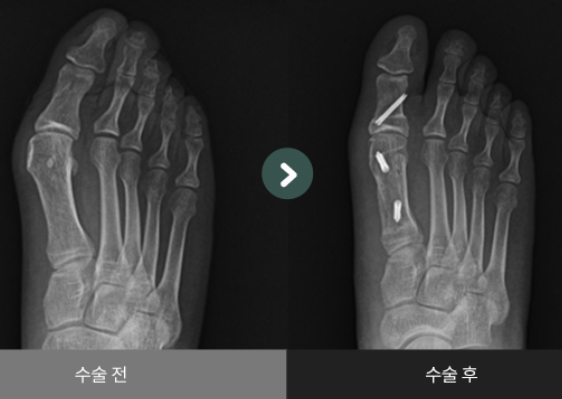

경미한 경우, 외반 모지는 신발 교체, 발가락 스페이서 착용, 맞춤형 교정기 사용 또는 처방된 약물 사용과 같은 보존적 치료로 관리될 수 있습니다. 이러한 치료가 효과적이지 않으면 수술이 권장될 수 있습니다. 무지외반증 수술은 발의 뼈를 재정렬하고 안정화시켜 통증을 줄이고 정상적인 발 기능을 회복시키는 것을 목표로 합니다.

무지 외반에 대한 가장 일반적인 수술 유형 중 하나는 연조직 박리술이라고 합니다. 이 시술에는 엄지발가락을 다시 정렬하기 위해 발 앞쪽의 힘줄과 인대를 절단하고 풀어주는 과정이 포함됩니다. 엄지 발가락의 뼈와 관절을 재정렬하기 위해 다른 유형의 수술도 수행될 수 있습니다.

- 이전에는 스카프와 쉐브론 교정술 같은 절골술(뼈를 자르는 수술)에 의존하였습니다.

- 평균 회복 기간은 8주 이상이며, 4~5cm의 피부 절개가 필요했습니다.

- 수술 후 통증이 심하고, 교정된 뼈의 강도가 약해 추가적인 금속핀, 나사 고정 및 이를 제거하기 위한 2차 수술이 필요했습니다.

- 경피적 도달법과 선택적 최소절골, 녹는 나사를 이용한 새로운 수술법이 개발되었습니다.

- 이 방법은 1mm의 작은 홈을 통해 수행되며, 수술 후 통증과 흉터가 줄어듭니다.

- 이 방법으로 교정된 뼈의 강도가 향상되어 6~8주간의 고정이 불필요하며, Resomet 녹는 나사를 사용하여 뼈의 정상 강도 회복이 가능합니다.